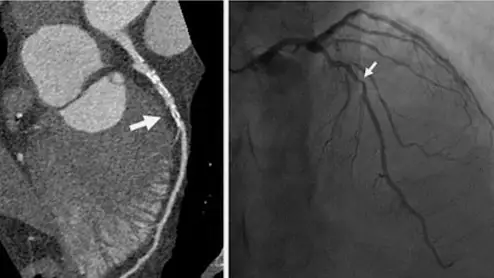

An example of a noninvasive coronary CT scan on the left and an invasive angiogram of the same patient on the right from a recent RSNA study. The CT shows more information on the calcified nature of the plaque and shows more anatomical information beyond what the angiogram provides.